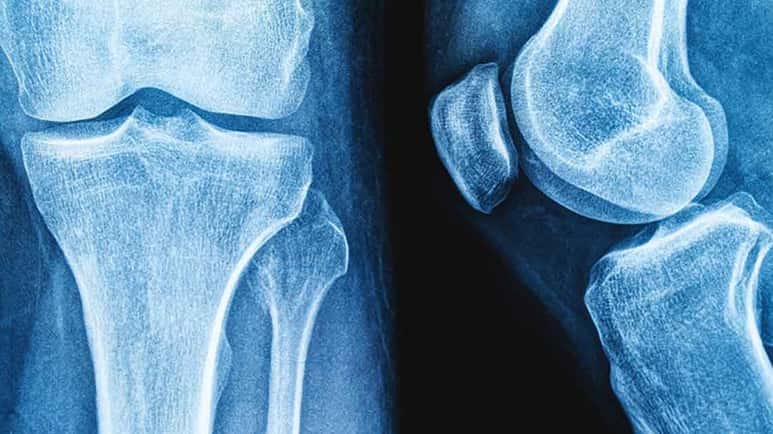

A narrative review published in the Osteoporosis International2 recently examined what happens when these microscopic plastic particles come into contact with the body’s strongest and most enduring structure — the bones. Their findings carry significant implications as bone-related diseases continue to rise worldwide, with the global incidence of osteoporosis-related fractures expected to rise by 32% by 2050.3

In the featured review, researchers from the State University of Campinas in Brazil analyzed 62 scientific papers to assess what is currently known about microplastics and skeletal health, including their links to bone diseases like osteoporosis. The review found that microplastics have been detected in human bone tissue and that experimental evidence points to multiple harmful effects on bone-forming and bone-resorbing cells.4

Animal studies confirm skeletal disruption — In animal experiments, microplastics were detected within bone tissue and bone marrow following exposure. The animals developed altered bone microstructures, including reduced growth and impaired trabecular formation, the lattice-like framework that provides strength and flexibility.

The skeletal system is enclosed and not in direct contact with environmental exposures,6 making the discovery of microplastics in bone tissue especially alarming. It raises pressing questions about how deeply these particles penetrate the body and the extent of the damage they leave behind.